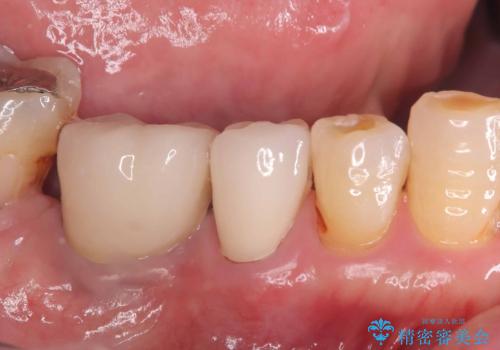

- 虫歯が原因で歯が欠けていました。昔詰めた保険の材料(CR)が劣化しその下が虫歯になっている状態でした。

色々な箇所にCR(保険の材料)を詰めてあったので、CRと虫歯を全部除去した後、オールセラミッククラウンで治療を行いました。

古いCR(保険治療で使用されるプラスチック)を除去すると残りの歯質が薄いため、破折抵抗を考慮しオールセラミッククラウンで治療を行いました。